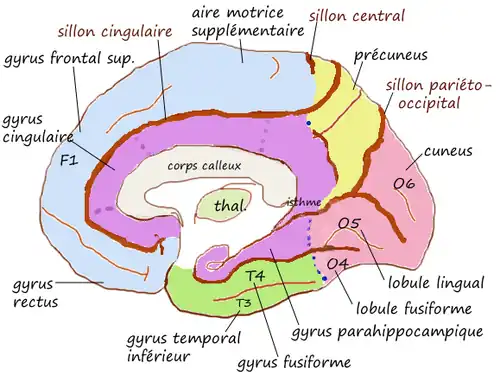

Le gyrus cingulaire est un gyrus du lobe limbique du cortex cérébral. Il est situé sur la face médiale des hémisphères, au-dessus du corps calleux. Au-dessus, il est séparé du gyrus frontal supérieur par le sillon cingulaire et du précuneus par le sillon sous-pariétal. En dessous, sa limite est le sillon du corps calleux. Au niveau du splénium du corps calleux, le gyrus cingulaire se rétrécit dans l'isthme qui se poursuit par le gyrus parahippocampique[1].

En latin, cingulum signifie « ceinture » (Gaffiot).

L'ensemble gyrus cingulaire, gyrus parahippocampique et diverses formations olfactives forment un anneau presque fermé qui s'appelle gyrus fornicatus (en latin, fornicatus signifie « voûté, cintré »).